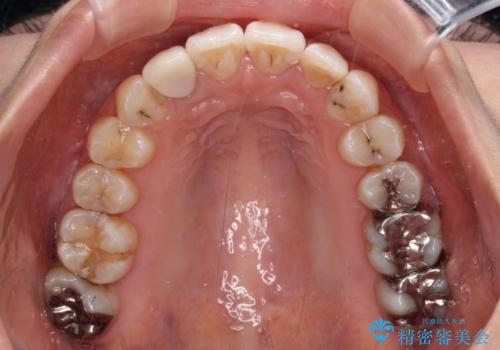

- 虫歯が多く、磨きにくい歯並びを改善したいとのことで来院された患者様です。

歯列は叢生が認められる程度でしたが、やや前突感があったので、少しでも口が閉じやすくなるように仕上げる方針としました。

神経を取り除かれている歯3本以外にも虫歯が認められたため、事前に処置を行い、インビザラインにて矯正治療を行うこととしました。

神経が取り除かれている歯は、クラウンによる補綴治療が必要であるため、矯正治療後にオールセラミッククラウンにて補綴治療を行うこととしました。

歯磨きしやすくなるとともに、飛び出していた前歯も引っ込めて整えることができました。